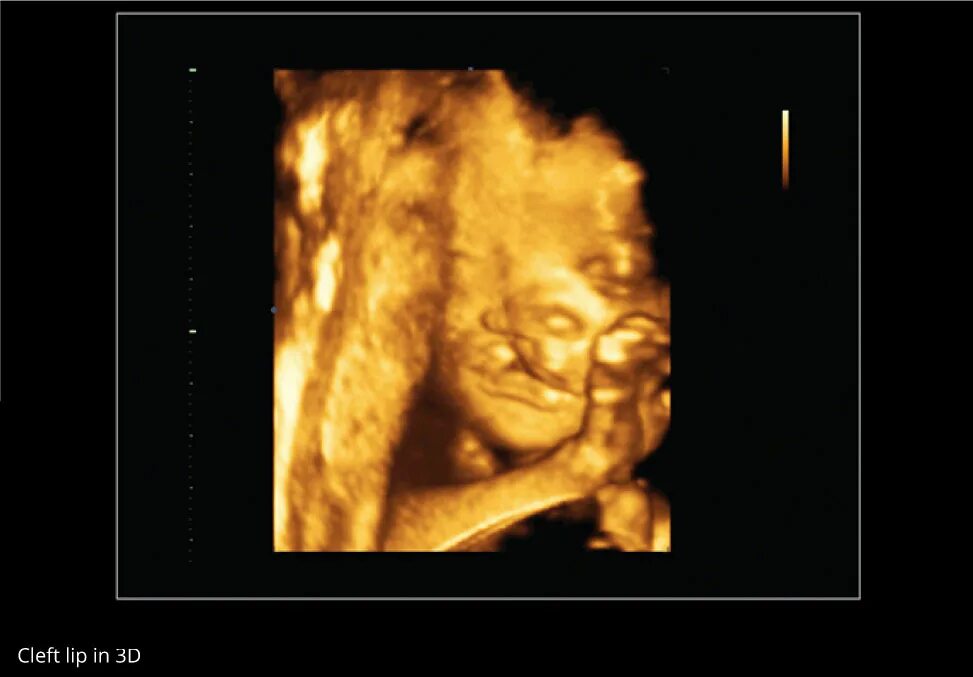

Второй скрининг 21 неделе